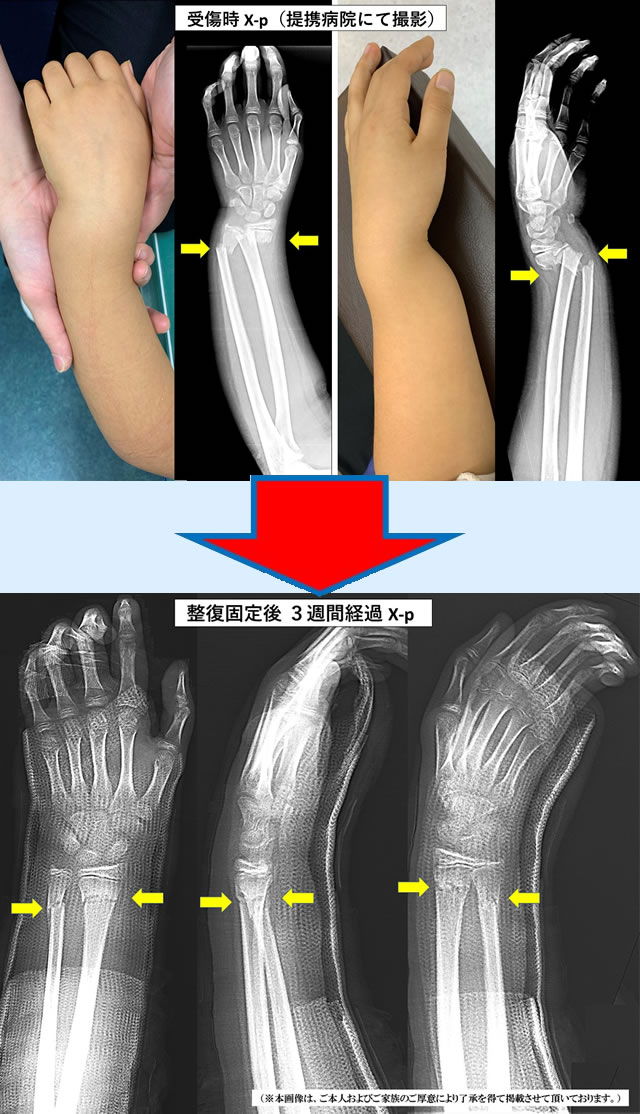

当院ではこのような患者様も徒手整復と固定管理により、手術を回避して、

後遺症なく早期に回復されております。

(※本画像・個人情報につきましては、ご本人およびご家族のご厚意により了承を得て、掲載させて頂いております。)

(9歳女児 左前腕両骨骨折)

9歳女児

左前腕両骨骨折

祝日に自宅で転倒した際に、手をついて負傷された患者様。写真で一目瞭然ですが、手首が骨折して強く変形していました。手術適応である程のひどい骨折でしたが、すぐに当院で処置(徒手整復・固定)を行うことができたため、手術を回避することができました。3週間ギプスで固定後、手首のリハビリを行い、受傷から6週間で完治。

今では後遺症もなく元気に遊んでいるとのことです。